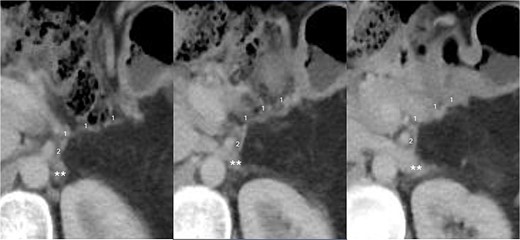

The final pathological examination revealed a 38 mm moderately differentiated ductal adenocarcinoma (T2). The 5/12 lymph nodes (N2) and lymphovascular and perineural invasion were positive, and the surgical margins were negative for malignancy. Thereafter, the patient received adjuvant treatment with FOLFIRINOX with adequate tolerance. Twelve months after surgery, there was no indication of venous congestion or recurrence of the disease, and the venous anastomosis continued to exhibit good patency (Fig. 3). Additionally, her CA19-9 level remained stable at 19.82 IU/ml.

CT scan taken 12 months after surgery, displayed from upper to lower in a left to right sequence, showing the anastomosis between the left gastric vein (LGV, 1) and left adrenal vein (LAV, 2). The left renal vein is indicated by ‘**’.